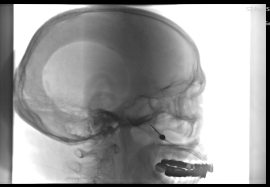

蝶腭神经节刺激